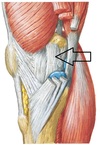

Popliteus